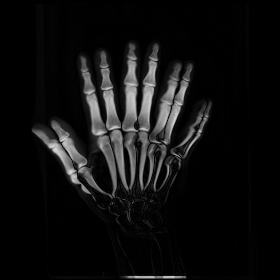

We then consider another example of registering two hand X-ray images with larger deformations (see Fig. 8(a) for the source image, Fig. 8(b) for the target image, and Fig. 8(c) for their absolute intensity difference). The warped image produced by our proposed method (Fig. 8(d)) again closely resembles the target image with the intensity difference significantly reduced (see Fig. 8(e)). Fig. 8(f) shows that the mapping is smooth and bijective. For comparison, note that LDDMM [5] fails to match the fingers (Fig. 8(g)). While DROP [18] is capable of registering the fingers (Fig. 8(h)), it distorts the boundary shape of the overall image (Fig. 8(i)).